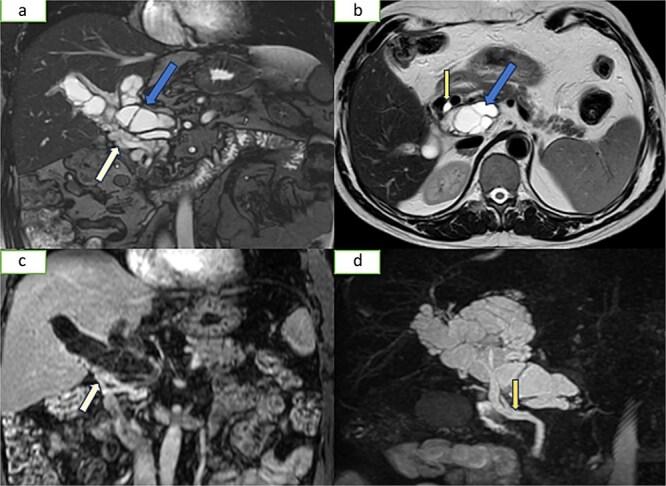

Hydatidosis, caused by , is a widespread parasitic disease, especially in livestock areas. In Morocco, it is hyperendemic and poses a major health concern. The liver and lungs are the most affected organs, but portal vein involvement is extremely rare, with only eight reported cases. We present a 56-year-old man with a recurrent hepatic hydatid cyst, three years after a left hepatectomy. Imaging revealed hydatid thrombosis of the portal vein, a rare complication requiring distinct management from typical venous thrombosis.

由……引起的包虫病是一种广泛传播的寄生虫病,尤其在牧区。在摩洛哥,它是高度流行的,并且是一个主要的健康问题。肝脏和肺是受影响最严重的器官,但门静脉受累极为罕见,仅有八例报告病例。我们报告一例56岁男性,在左肝切除术后三年出现复发性肝包虫囊肿。影像学检查显示门静脉包虫血栓形成,这是一种罕见的并发症,需要与典型的静脉血栓形成进行不同的处理。 (原文中“caused by ”后缺少具体病因信息)